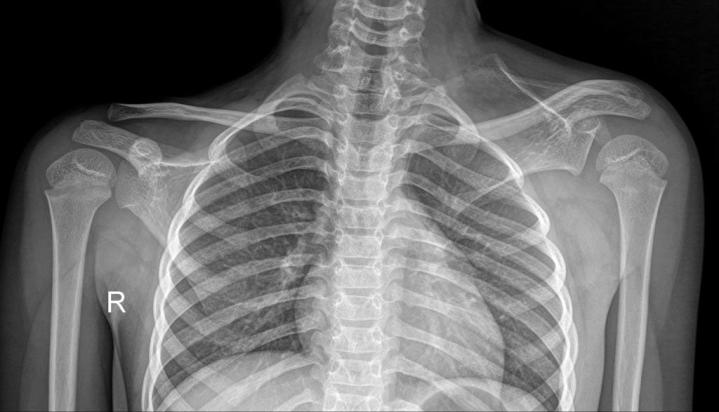

fibrodysplasia ossificans progresive

aka Stone Man Disease is a congenital disorder, it’ll kill you, and it’s basically extensive heterotopic ossification in the soft tissues.

massive bizarre heterotopic ossification

Sprengel deformity! Associated with Klippel-Feil